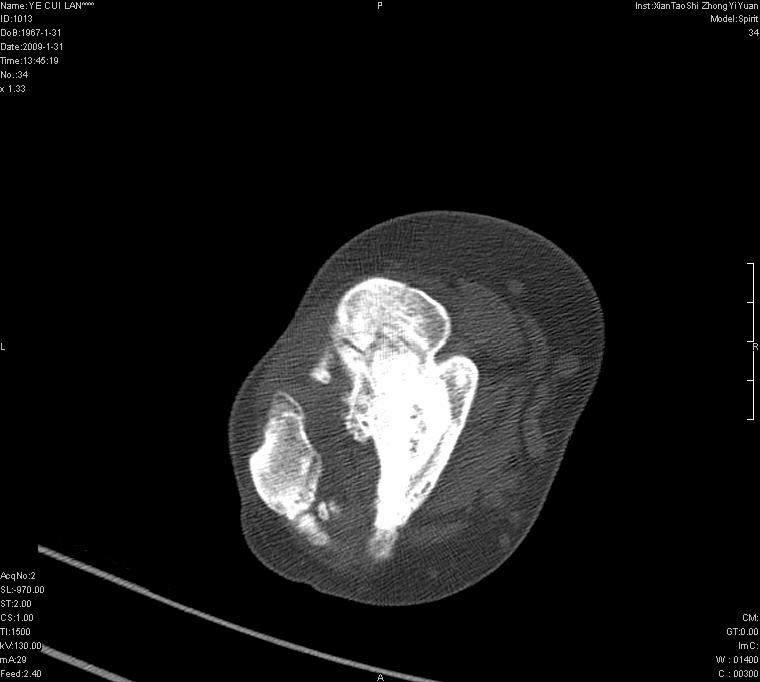

以下是引用王明发在2009-2-9 11:53:00的发言:[br]支持夏科氏关节,必要时行脊髓mri检查 [br]夏科氏关节是指由于某些神经系统疾病引起的关节病变,也被称为神经性关节炎。常见病因有脊髓痨、脊髓空洞症等。原发的神经病变可以造成关节深部感觉障碍,对于关节的震荡、磨损、挤压、劳倦不能察觉因而也不能自主地保护和避免,而神经营养障碍又可使修复能力低下,使病人在无感觉状态下造成了关节软骨的磨损和破坏,关节囊和韧带松弛无力,易形成关节脱位和连枷关节。关节面的破坏和骨赘的脱落变成关节内游离体。关节外形饱满肿胀,内有出血和渗出。这种病早期并无疼痛,不易被病人重视,仅表现为关节肿胀、无力、活动过度、动摇不稳。关节肿胀、无痛、活动范围超常是本病的重要特征。x光片可见有关节骨端广泛破坏、硬化或呈奇异形态,骨赘形成,关节间隙不规则或增宽,周围软组织钙化、关节内游离体、骨碎片等。结合x光片及临床症状,病人又有神经系统原发病症,即可确诊

以下是引用hhcckk在2009-2-9 14:31:00的发言:[br]夏科关节的六大表现[br]1.关节软组织肿胀。[br]2.关节的脱位与半脱位。[br]3.关节内的游离体。[br]4.关节面硬化,新骨形成。[br]5.骨质萎缩与破坏。[br]6.关节结构的紊乱。[br]加上患者无明显疼痛,诊断的把握性比较大